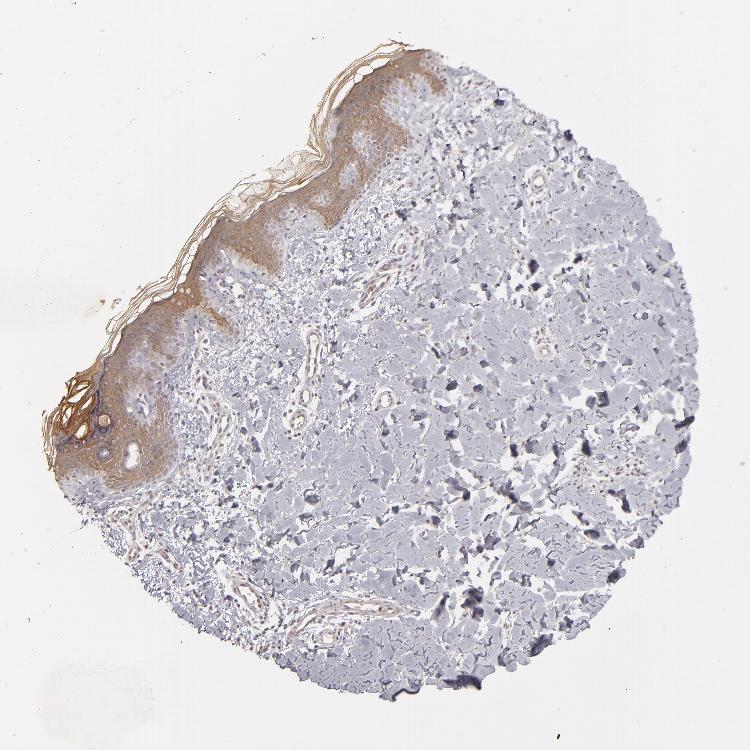

SKIN 1 - Antibody stainingi

Antibody staining in the annotated cell types in the current human tissue is reported as not detected, low, medium, or high, based on conventional immunohistochemistry profiling in selected tissues. This score is based on the combination of the staining intensity and fraction of stained cells.

Each image is clickable and will lead to virtual microscopy that enables deeper exploration of all samples and also displays staining intensity scores, fraction scores and subcellular localization as well as patient and tissue information for each sample.

Antibody HPA018859Antibody HPA019938Antibody HPA025230Antibody CAB002679

Langerhans -Not detectedMediumLow

Cells in basal layer Low---

Cells in corneal layer Not detected---

Cells in granular layer Not detected---

Cells in spinous layer Low---

Eccrine glands Low---

Endothelial cells Low---

Extracellular matrix Not detected---

Fibroblasts -Not detectedMediumNot detected

Fibrohistiocytic cells Low---

Hair follicles Low---

Keratinocytes -LowMediumMedium

Langerhans cells Low---

Lymphocytes Low---

Melanocytes Not detectedLowMediumNot detected

Sebaceous glands Low---

Vascular mural cells Not detected---